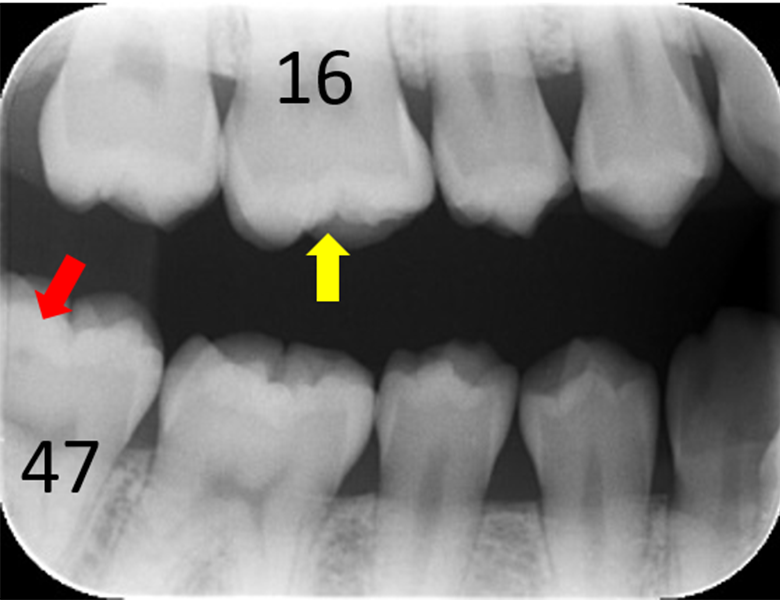

症例① 上顎大臼歯 小窩や裂溝の虫歯 20歳女性

※小窩や裂溝:歯の咬み合せ面にある複雑なくぼみや溝のこと

初診時口腔内写真 |

![]() 初診時レントゲン写真 |

症例①②

主訴 |

正しい口腔ケアを知り、健康的になりたい。 |

診断 |

上下大臼歯の初期虫歯 |

治療 |

経過観察 |

期間 |

経過観察中 |

費用 |

0円 |

治療リスク |

虫歯進行の可能性 |